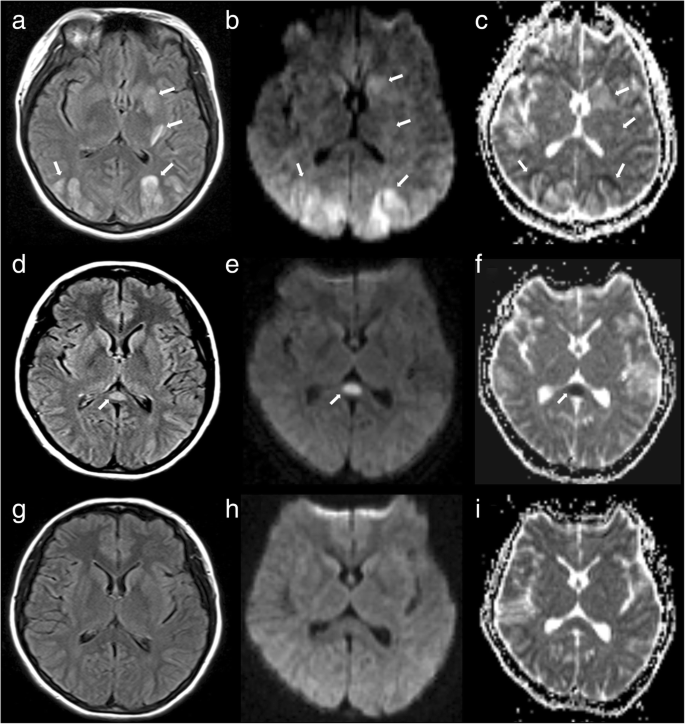

A 23-year-old pregnant woman without any history of hypertension or migraine suddenly developed a thunderclap headache, dizziness, and eye pain at 35 + 2 weeks of gestation. She did not take these symptoms seriously and also experienced one episode of vomiting without fever and syncope. By the afternoon of the same day, her symptoms worsened, and she was admitted to the emergency department with a complaint of mistiness of vision in both eyes. At the time of admission, her blood pressure was 170/110 mmHg. Neurological examination revealed no abnormal signs such as hemiparesis and seizures. Serological laboratory tests showed no autoimmune conditions or infectious pathogens such as bacteria and viruses. Brain MRI performed on the same day revealed symmetric lesions in the posterior circulation territories, including the bilateral parietooccipital lobes, left basal ganglia, and corona radiata. These lesions showed hyperintensity on T2-weighted imaging and fluid-attenuated inversion recovery (FLAIR) imaging (Fig. 1a). DWI (Fig. 1b) and ADC mapping (Fig. 1c) revealed mild hyperintensity in the lesions, which indicated vasogenic cerebral edema. The patient was diagnosed with eclampsia-associated PRES and received intravenous infusion of mannitol (125 ml; q8h × 8 days) for the management of intracranial hypertension. On the same day, cesarean section was successfully performed, and her blood pressure decreased to 154/103 mmHg one hour after surgery. However, she complained of headache and bilateral blindness. On the day after surgery, her headache ameliorated, vision improved, and blood pressure decreased to 140/85 mmHg. Ten days later, i.e., one day after the withdrawal of mannitol, FLAIR imaging, DWI, and ADC mapping showed that the hyperintense lesions (vasogenic edema) had disappeared. However, an isolated lesion with restricted diffusion that showed a high signal in DWI and a low ADC value (cytotoxic edema) was observed in SCC; these findings indicated RESLES type I) [6]. Five days after the discontinuation of mannitol, she showed no abnormal symptoms and was discharged from our hospital. Follow-up brain MRI performed 29 days the clinical onset of symptoms showed no abnormalities (Fig. 1g–i).

Brain magnetic resonance (MR) images for a 23-year-old woman with eclampsia who presented with sudden-onset headache, dizziness, and severe hypertension (blood pressure, 170/110 mmHg). a–c. Axial brain MR images obtained at the clinical onset of symptoms show vasogenic cerebral edema in the bilateral parietooccipital lobes, left basal ganglia, and corona radiata. Fluid-attenuated inversion recovery (FLAIR) imaging (a), diffusion-weighted imaging (DWI; b = 1000; b), and apparent diffusion coefficient (ADC) mapping (c) show mild hyperintensity in the lesions (arrows), which is a typical finding in posterior reversible encephalopathy syndrome (PRES). d–f. Follow-up MR images obtained 10 days after the clinical onset of symptoms (i.e., 1 day after withdrawal of mannitol show that the originally observed hyperintense lesions have disappeared (vasogenic edema has disappeared). FLAIR imaging (d) shows an isolated hyperintense signal in the splenium, whereas DWI (e) and ADC mapping (f) show restricted diffusion in the splenium (arrows), which is a typical finding in reversible splenial lesion syndrome. g–i. Follow-up MR images obtained 29 days after the clinical onset of symptoms FLAIR imaging (g), DWI (h), and ADC mapping (i) show that the lesions in the splenium have disappeared